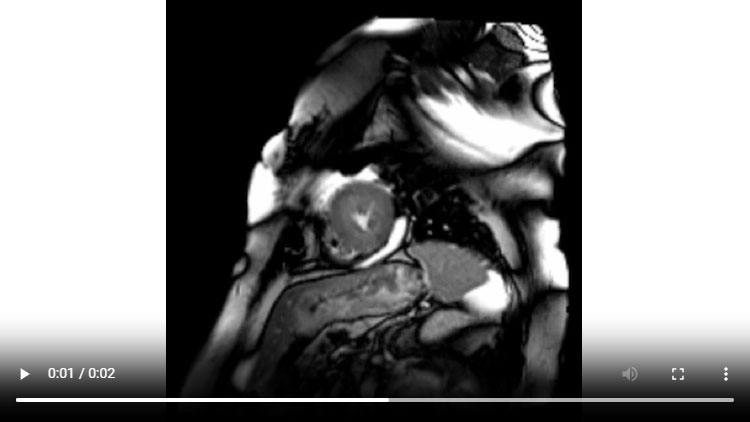

Figure 1C : Séquence Ciné-IRM - Coupes petit-axe apical

- Présence d’une hypertrophie ventriculaire gauche (HVG) asymétrique à prédominance septale mesurée au maximum à 23 mm.

- Visualisation de la sonde de PM avec artéfacts métalliques modérés au niveau du ventricule droit (flèches roses).

- Présence d’un épanchement péricardique de moyenne abondance (flèches rouges).